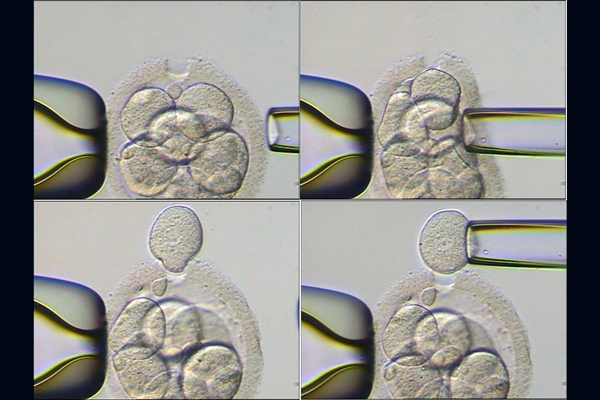

Я дотошный пациент)) Мне врач показывал фото-картинки ооцитов оплодотворенных ИКСИ и естественно, когда ИКСИ он снаружи гладкий, когда естественное оплодотворение он снаружи как "ежик". Вот этот ежик внешний и содержит днк спермиков которые не успели оплодотворить ооцит и когда делают биопсию, то цепляют "все в куче". Подруга делала ПГД в Мид на Савеловской в 2016г, было Икси+пгд

Вот на картинке видно что берут бластомер для анализа ПГД. Может мы с вами про разные вещи говорим???

Даже на фото это видно. Они делают надрез в на оболочке типа лунки-колодца. И выдавливают один бластомер. Выходя бластомер проходит по чистой лунки где нет оболочки а соответственно и следов от других спермиков. Через несколько часов эта лунка заростает.

вот такой "ежик"